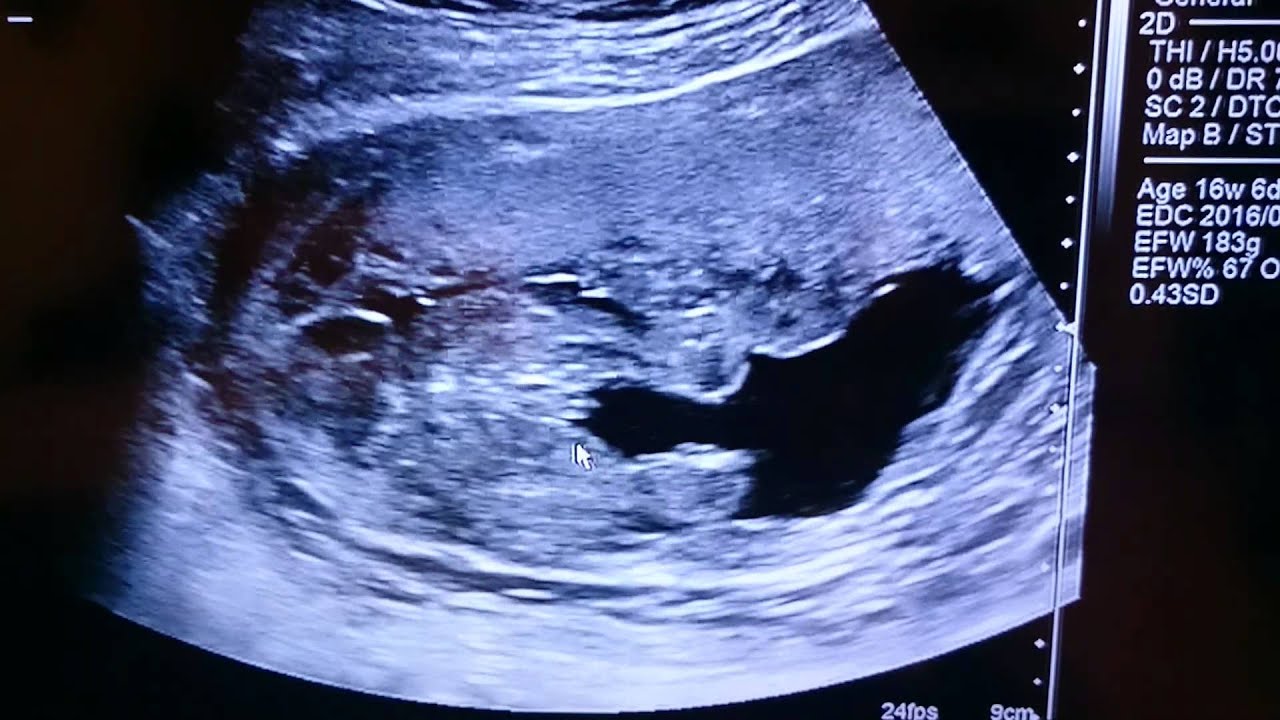

17 週 エコー 男の子-18 週 エコー 男の子 pricing &くろみつさんの妊娠18週目のエコー写真 男の子と判明し、「タロー」と命名 エコー画像で振り返る、私に宿った小さな命が大きく育って誕生するまでの記録 上半身の4D画像です。 右手を頭に、左手を頬に置いている姿がなんともかわいらしく映ってい

妊娠18週目 18w0d 6d のエコー写真とエピソード 妊娠5ヶ月 Cozre コズレ 子育てマガジン